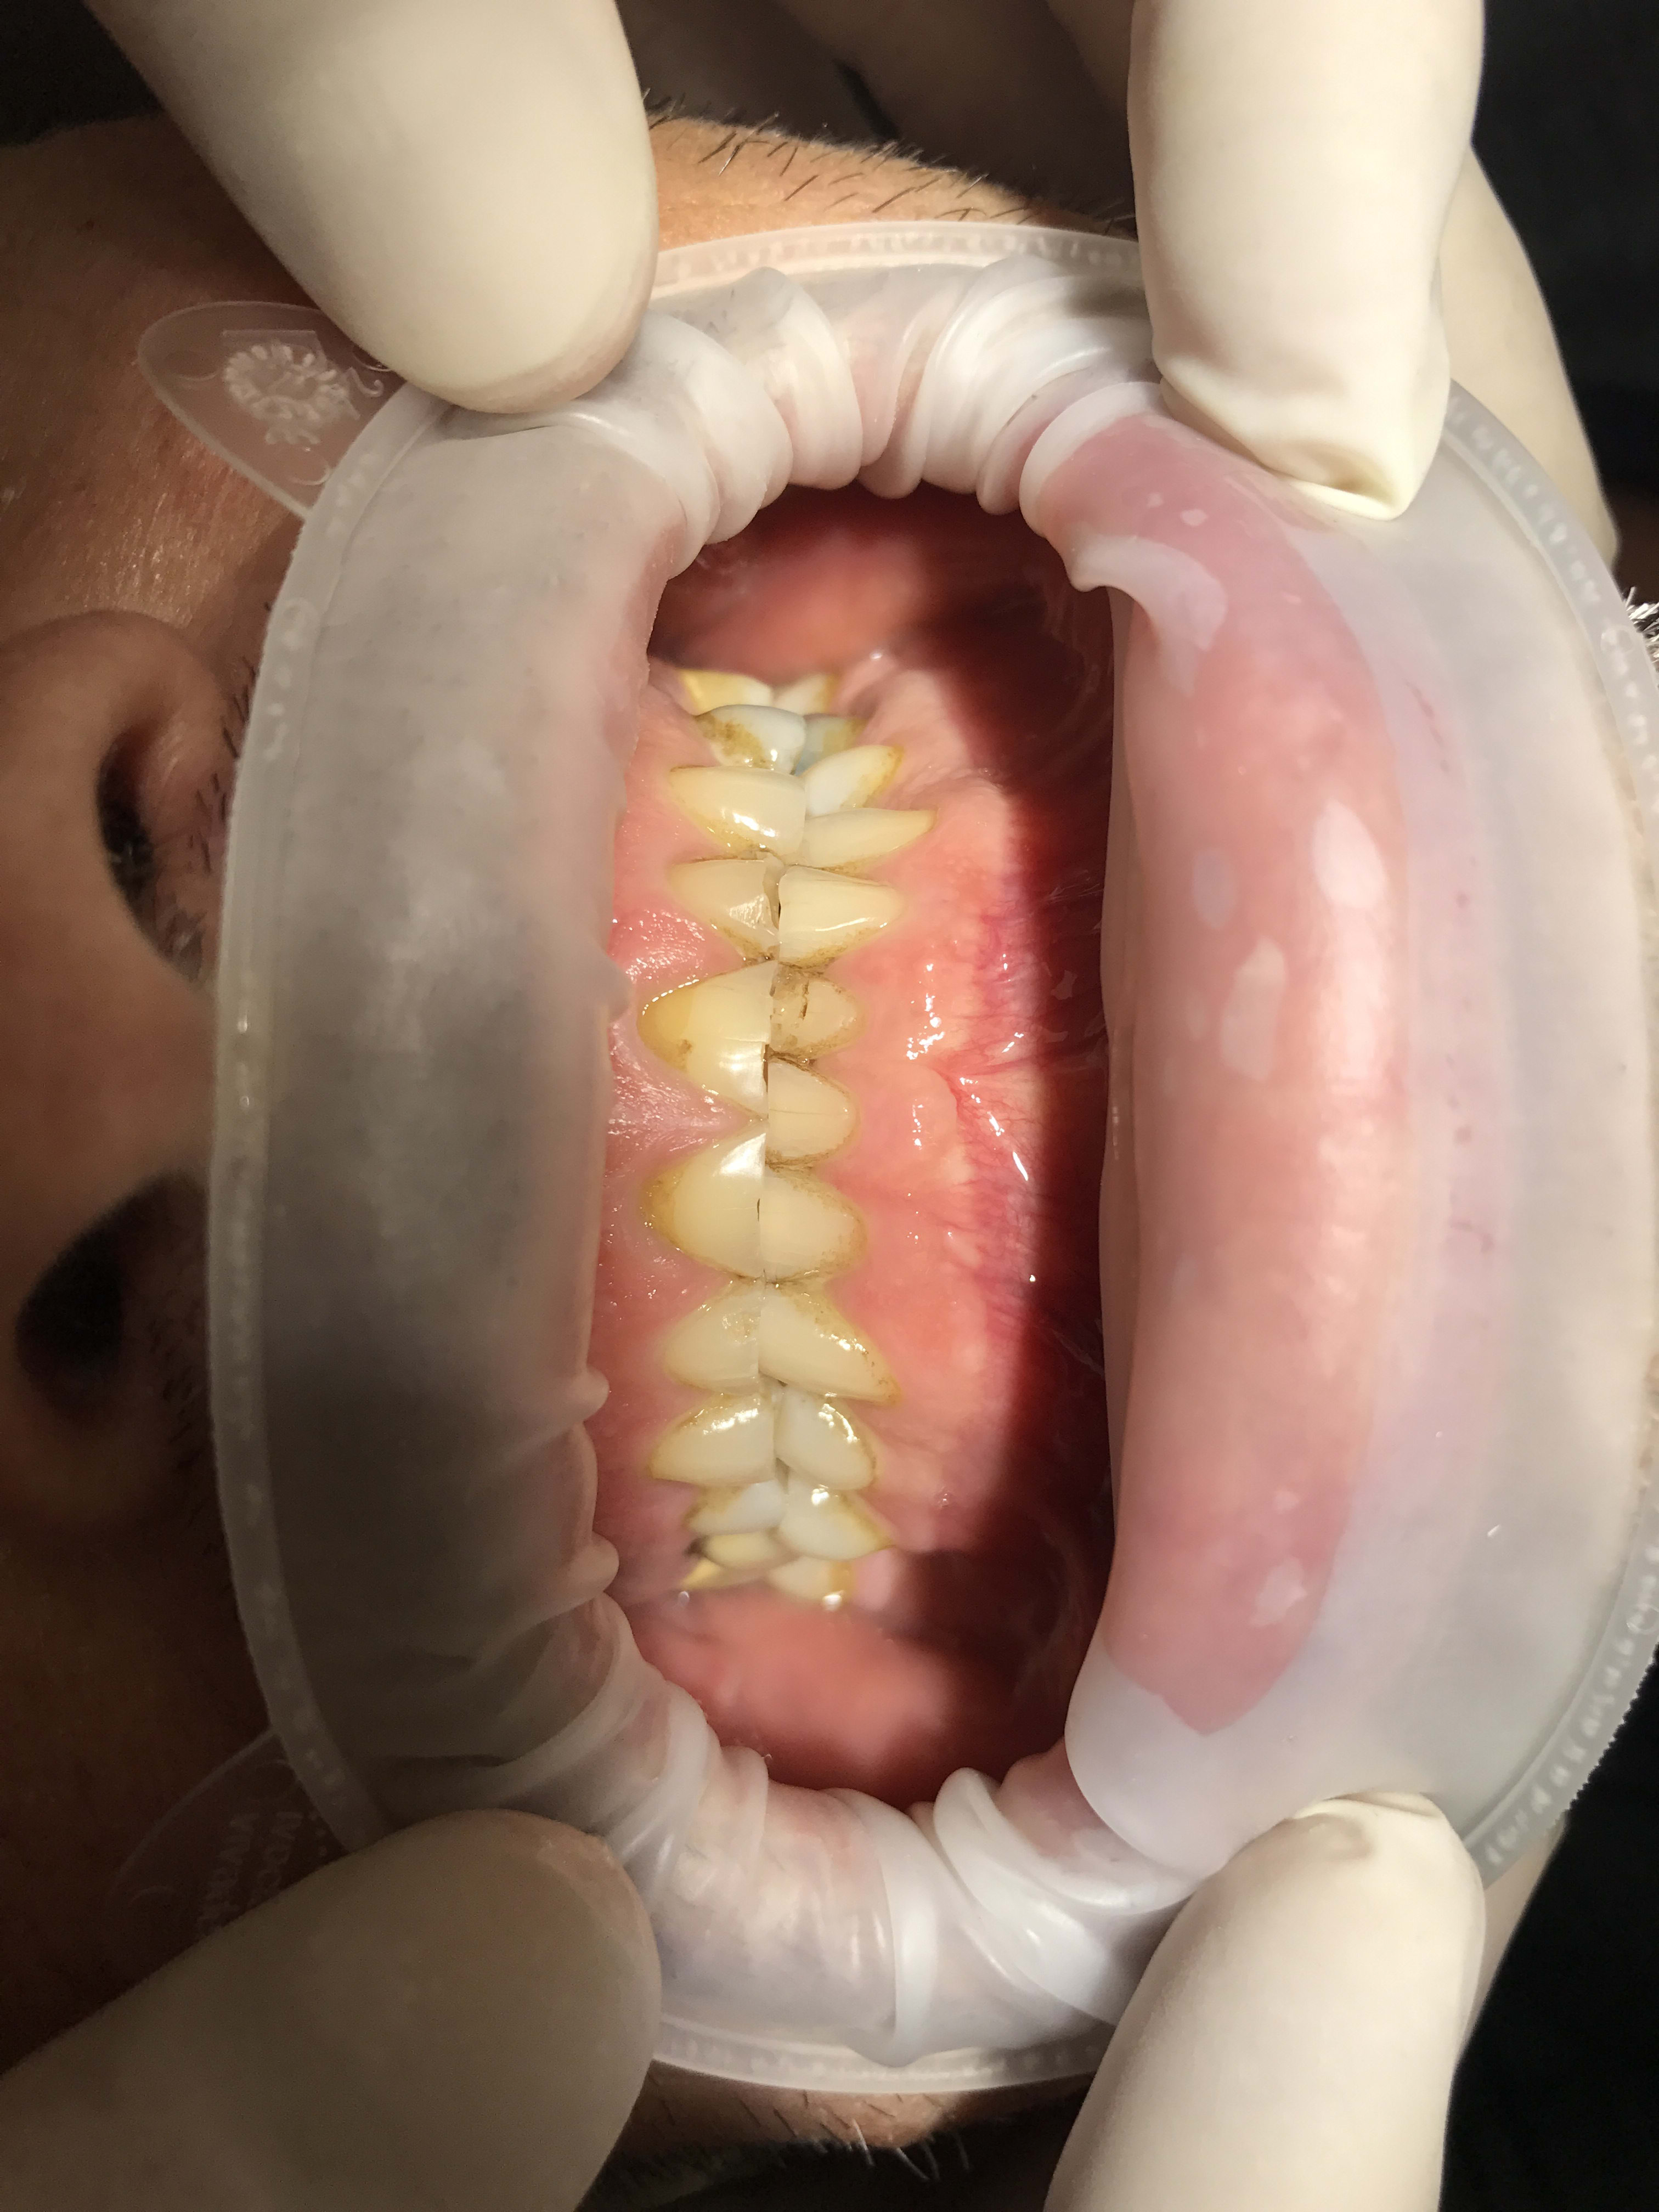

Restauration globale sur un patient qui bruxe?

Cela fait bien longtemps qu'il bruxe et a usé toutes ses dents, n'a plus de calage.

Je pensais faire suite au rte et à la pose des implants un wax up mock up avec facettes en antérieure et table top/couronnes en postérieur, et augmentation de la dvo de plusieurs mm.

Tu feras gaffe, ton patient a les dents du bas en haut.